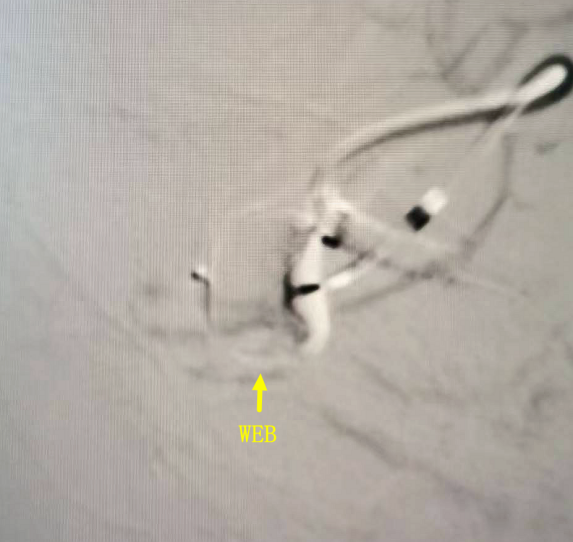

近日,面对一位古稀老人颅内破裂的“不定时炸弹”——复杂脑动脉瘤,我院神经外科团队成功应用全球前沿的自膨式动脉瘤瘤内栓塞器(WEB) ,完成了我院首例该技术下的动脉瘤精准介入治疗。 紧急救治 古稀老人突发“颅内炸弹” 71岁的张先生(化名)突发剧烈头痛伴右侧肢体乏力,经120紧急送入我院。急诊迅速启动卒中绿色通道,经头部CT及CTA检查,诊断为“广泛蛛网膜下腔出血、左侧大脑中动脉分叉部动脉瘤”。此类动脉瘤破裂风险极高,如同颅内的“不定时炸弹”,治疗刻不容缓。 术前颅脑CT见广泛蛛网膜下腔出血 CTA见左侧大脑中动脉分叉部宽颈动脉瘤 创新破局 全球新技解难题 神经外科介入团队立即组织多学科讨论,详细研判病情,制定了开颅夹闭与微创介入栓塞两套方案,家属明确选择微创手术方案。面对位于复杂分叉处且瘤颈宽大的动脉瘤,团队决定应用全球前沿的自膨式动脉瘤瘤内栓塞系统(WEB)进行治疗。在神经外科、介入中心与麻醉科的通力协作下,成功将自膨式动脉瘤瘤内栓塞系统(WEB)装置植入动脉瘤腔内,完成栓塞治疗,历经2小时。术后,造影显示动脉瘤完全隔绝,载瘤动脉通畅良好,危机解除。 技术优势 瘤内扰流新选择 自膨式动脉瘤瘤内栓塞系统(WEB)装置形似精密编织的迷你网篮,专为分叉部宽颈动脉瘤设计。相较于传统支架辅助栓塞,自膨式动脉瘤瘤内栓塞系统(WEB)技术体现了神经介入领域的重要创新: 操作简化: 单一器械即可完成治疗,流程更简洁。 安全性提升: 避免支架植入,降低了血栓等并发症风险。 患者受益: 术后无需长期服用抗血小板药物,减轻了身心及经济负担。 此例自膨式动脉瘤瘤内栓塞系统(WEB)植入术的成功开展,标志着我院在复杂脑动脉瘤微创治疗领域取得新突破,为患者提供了高效的治疗选择。作为国家卫健委能力建设和继续教育神经外科建设中心,贵州航天医院神经外科将持续依托优质资源,深化对外协作,以技术创新护航百姓健康。 神经外科专家简介 廖洪民 神经外科党支部书记、主任,主任医师 临床擅长:从事神经外科临床工作30年,对颅脑损伤、脑肿瘤、脑血管病等具有丰富诊疗经验,擅长救治重症颅脑创伤、脑出血微创治疗、脑肿瘤显微手术治疗、脑立体定向手术等。 中国医师协会神经外科分会专科认证医师、贵州省医学会神经外科分会青年委员、遵义市医学会神经外科分会常务委员、遵义市中西医结合学会脑心同治专业委员会常务委员、中国生命关怀协会脑卒中救治及康复照护专业委员会委员、贵州省脑损伤评价质控中心专家库成员、遵义市脑损伤评价医疗质量控制中心专家。 朱家伟 神经外科副主任医师 临床擅长:从事神经外科工作26年,擅长颅脑损伤救治及脑出血微创手术。 遵义市医学会神经外科分会委员、遵义市中西医结合学会脑心同治专业委员会常务委员。 黄建军 神经外科副主任医师 临床擅长:从事神经外科工作20年,对神经外科常见病、急危重症有丰富诊疗经验,熟练掌握神经外科微创手术。 神经外科科室简介 基本情况 贵州航天医院神经外科于2008年独立建科,是首批国家卫健委能力建设和继续教育神经外科建设中心,贵州省神经外科介入联盟单位。现有专业技术人员17人,其中高级职称4人,中级5人,初级7人。 科室配备STORZ神经内镜系统、德国莱卡手术显微镜,国产西山开颅动力系统、蛇牌双极电凝、Mayfield头架等颅脑手术设备,以及无创和有创颅内压监护仪、正中神经刺激仪、脑循环康复治疗仪、排痰机、下肢康复训练器、气垫床、多参数监护仪等现代化医疗设备,为病区各种急、危、重患者的观察、监护和治疗保驾护航。 专科特色 (一)脑出血微创手术治疗 应用范围:各种病因导致的自发性脑出血(高血压脑出血、脑淀粉样血管病相关脑出血、抗凝药物相关脑出血等)。 技术优势:微创、精准、恢复快。 (二)颅脑病变显微切除术 应用范围:颅内各种占位性病变(脑囊肿、脑肿瘤等)。 技术优势:精确度高、创伤小、恢复快。 (三)颅脑创伤综合救治 应用范围:各种类型的颅脑损伤、创伤性颅内血肿及颅脑创伤并发症、后遗症等。 技术优势:快速精准诊断、个体化手术与监护、早期康复干预,伤者病死率低、并发症少。